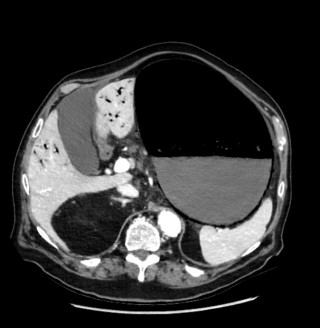

A 77-year-old man with a history of arterial hypertension, chronic alcohol use, gait disorders, and umbilical hernia repair, was admitted with acute left upper quadrant pain and repeated vomiting. Upon admission, vital signs where stable, but clinical exam revealed abdominal distension with peritoneal signs. An abdominal computed tomography scan (Figure 1) showed marked gastric distension, parietal pneumatosis and portal and mesenteric vein gas along with small bowel ileus, without signs of perforation. Additionally, a lesion in the right colonic’s flexure raised suspicion of a neoplasic lesion.